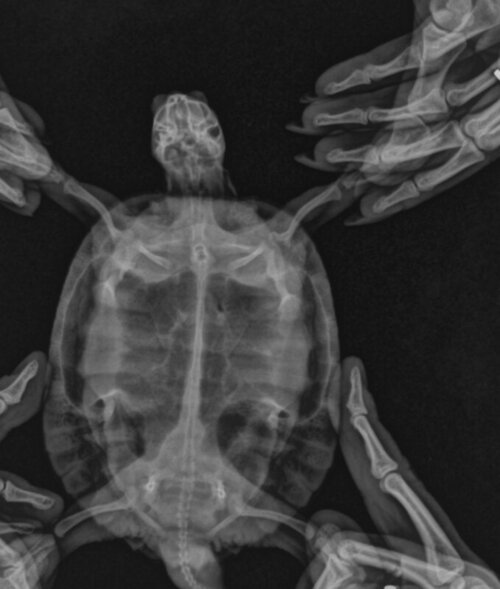

Консультанты moth Ваше имя: Мария Локация: Москва Опубликовано: 4 сентября 2019 Консультанты Опубликовано: 4 сентября 2019 @Юля48 по рентгену у него кал просто стоит и не двигается. Там либо закупорка либо по какой-то причине не работает жкт. Попробуйте ещё раз рентген сделать после масла посмотреть - есть хоть какая-то динамика или нет. У него так перитонит разовьётся и всё.